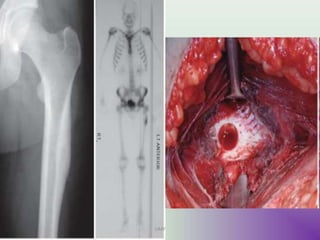

RADIOLOGY

Type of Osteolysis

• Geographic destruction (I)

• Moth-eaten (II) Permeative(III)

Lodwick

• Expansile

• TRABACULATION

PURE LYTIC (60%) FINE TRABACULTION(40%)

SCINTI GRAPHY

Less useful

Inconsistent uptake

“Doughnut sign”

M.R.I.

Soft tissue spread

Joint breach

Locate N.V. bundle

T1-Dark,T2-Bright

ABC-20%

C.T

Intraossous content

Intra articular spread

Cortical breach

Site of window

ANGIO GRAPHY

Locate vessels

type of feeders

For embolisation

INVESTIGATIONS